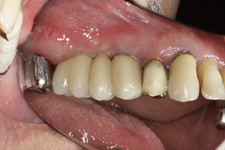

Protetické řešení může být pomocí můstku, který je kotvený na implantátech nebo pomocí jednotlivých korunek na implantátech.

V zásadě je možné do těchto můstků zařadit i přirozené zuby, zejména pokud je potřeba tyto zuby ošetřit proteticky - korunkami. Korunky nebo můstky mohou být na implantáty nacementovány nebo přišroubovány.

Zdravé zuby zůstanou zachovány a přitom náhrady jsou pevné, jako na vlastních zubech